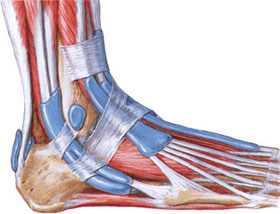

• Таранная кость сочленяется с большеберцовой, малоберцовой, ладьевидной и пяточной костями

• В подтаранном суставе выделяют три отдела: задний, средний и передний:

о Задний отдел является наибольшим; несет 50% от всей нагрузки на подтаранный сустав

• Задний большеберцовый нервно-сосудистый пучок проходит позади медиальной лодыжки, а затем через канал предплюсны

Человеческая стопа состоит из 26 костей, образующих три отдела: предплюсна, плюсна и фаланги пальцев. В состав предплюсны входит 7 костей: таранная, пяточная, ладьевидная, кубовидная и три клиновидных (латеральная, промежуточная и медиальная).

В голеностопном суставе кости голени сочленяются с таранной костью, причем нижние концы костей голени (лодыжки) охватывают таранную кость с боков, образуя своеобразную вилку. Голеностопный сустав укреплен суставной капсулой и развитым связочным аппаратом. Дистально (дальше от центра) предплюсна соединяется с пятью трубчатыми костями плюсны. Предплюсно-плюсневые суставы малоподвижны. Плюсневые кости соединяются с фалангами пальцев.